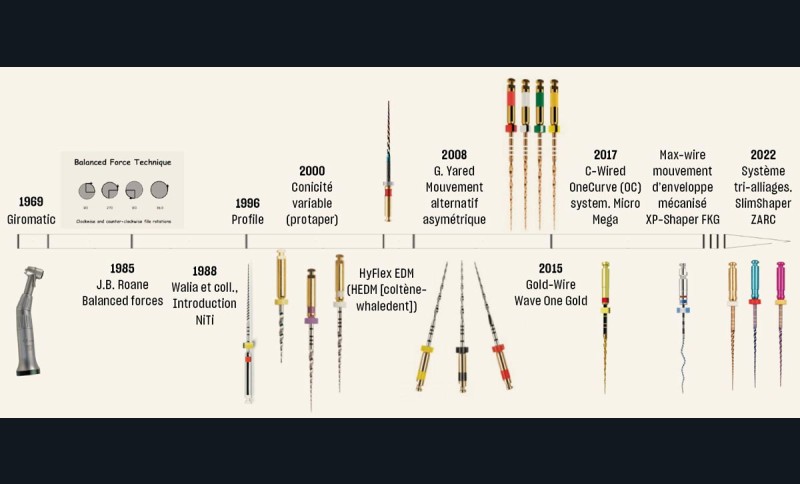

L’évolution des instruments au service de l’endodontie raisonnée

Depuis une trentaine d’années, le nickel-titane (NiTi) est devenu incontournable quand il s’agit de l’étape de mise en forme en endodontie. Il est notamment reconnu pour ses propriétés super–élastiques et de mémoire de forme [18]. Plus récemment, les fabricants ont ajouté des traitements thermiques post-usinage dans les procédés de fabrication des instruments. En fonction des cycles de températures appliqués, de nouvelles couleurs de NiTi sont apparues : Gold wire (par ex. WaveOne Gold®), Blue wire (par ex. Reciproc Blue®), Pink Wire : (par ex. SlimShaper®) (fig. 10), etc. Ces traitements thermiques post-usinage procurent de nombreux avantages à l’instrument, tels que la résistance à la fatigue cyclique, la flexibilité, l’efficacité de coupe et la capacité de centrage dans le canal [19-20].

Les systèmes de mise en forme deviennent moins invasifs, plus respectueux des parois canalaires, avec des conicités réduites < 6 % (par ex. XP-endo Shaper®, TrunatomyTM, SlimsShaper®). La « relocalisation de l’orifice canalaire » et la destruction des structures dentinaires saines (péri-cervicale et intracanalaire) disparaissent peu à peu des procédures de mise en forme, réduisant ainsi le risque d’effets iatrogènes tels que la fracture radiculaire [21].